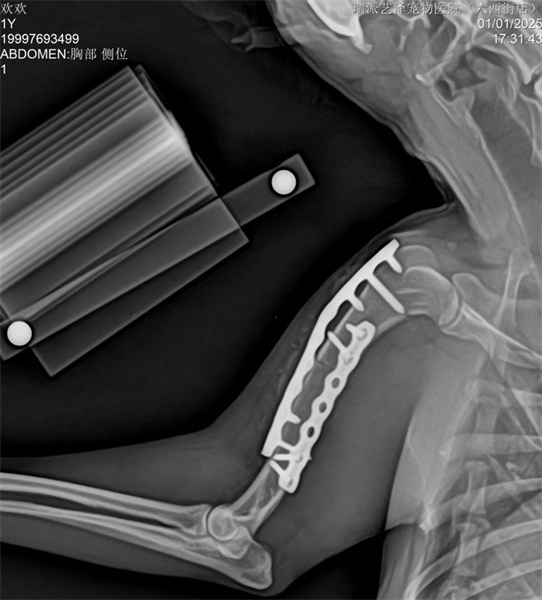

The tibia adopts the medial MIPO surgical approach to protect soft tissue as much as possible, and is fixed using intramedullary nails and bridging bone plates.

The tibia adopts PRCL8mm bone plate and 2.5mm needle, ensuring that there are at least two screws at the proximal and distal ends